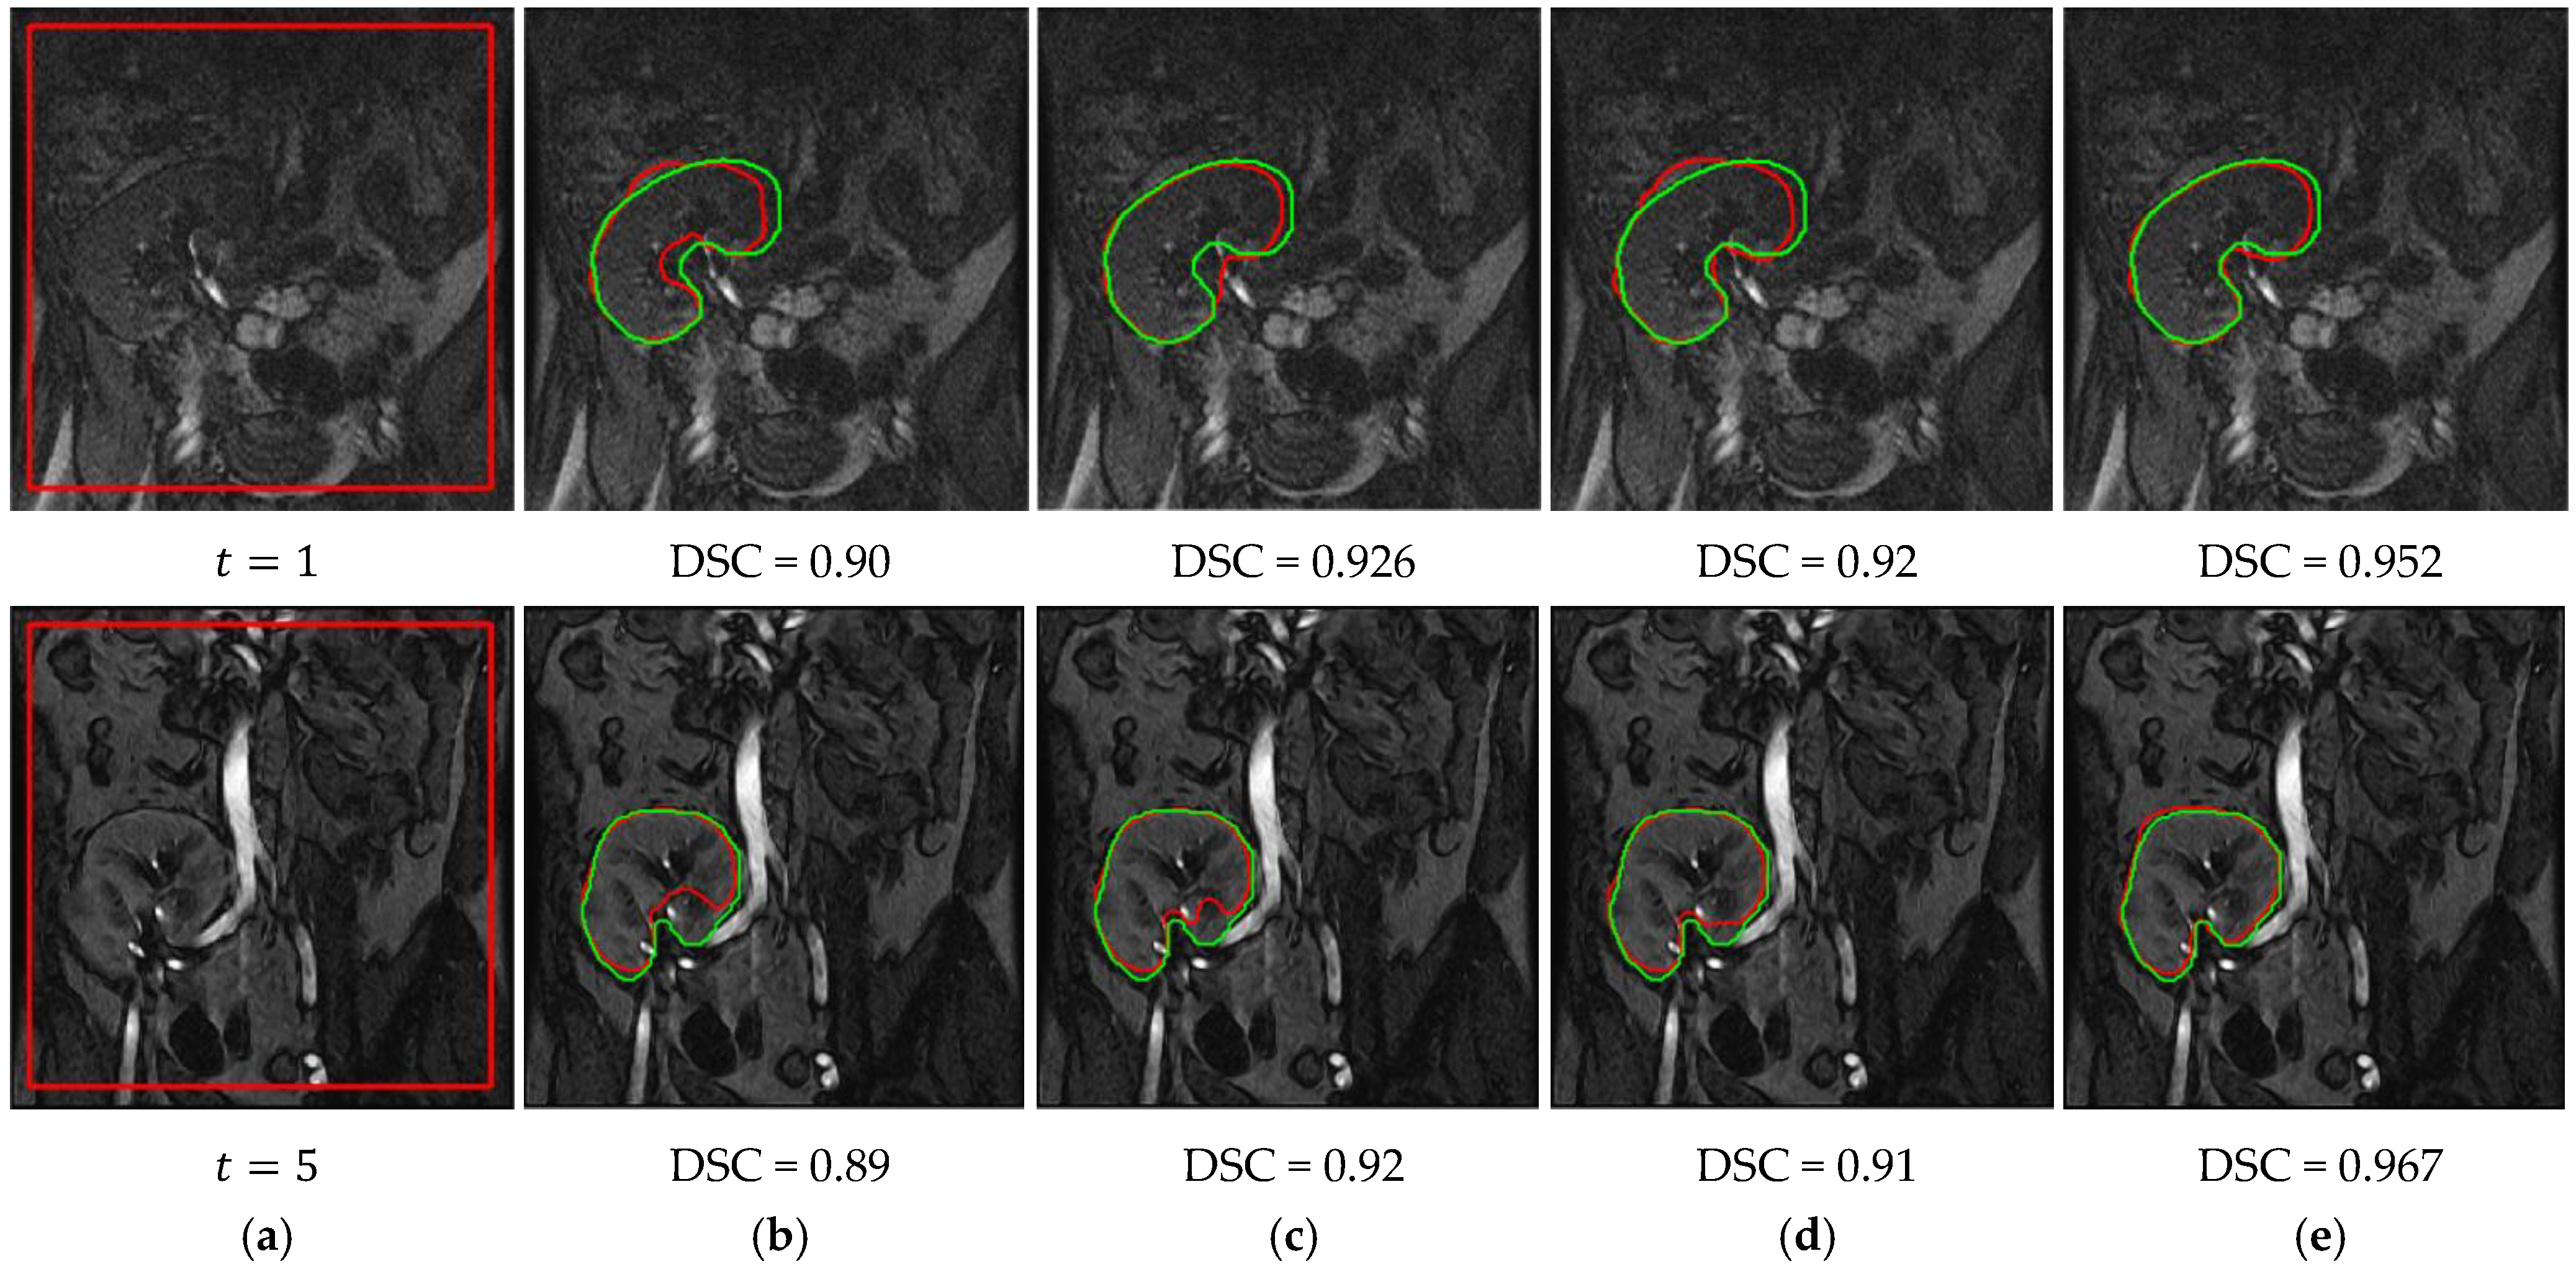

3.1. Method Performance with Comparisons to Other Methods

3.2. Ablation Experiments